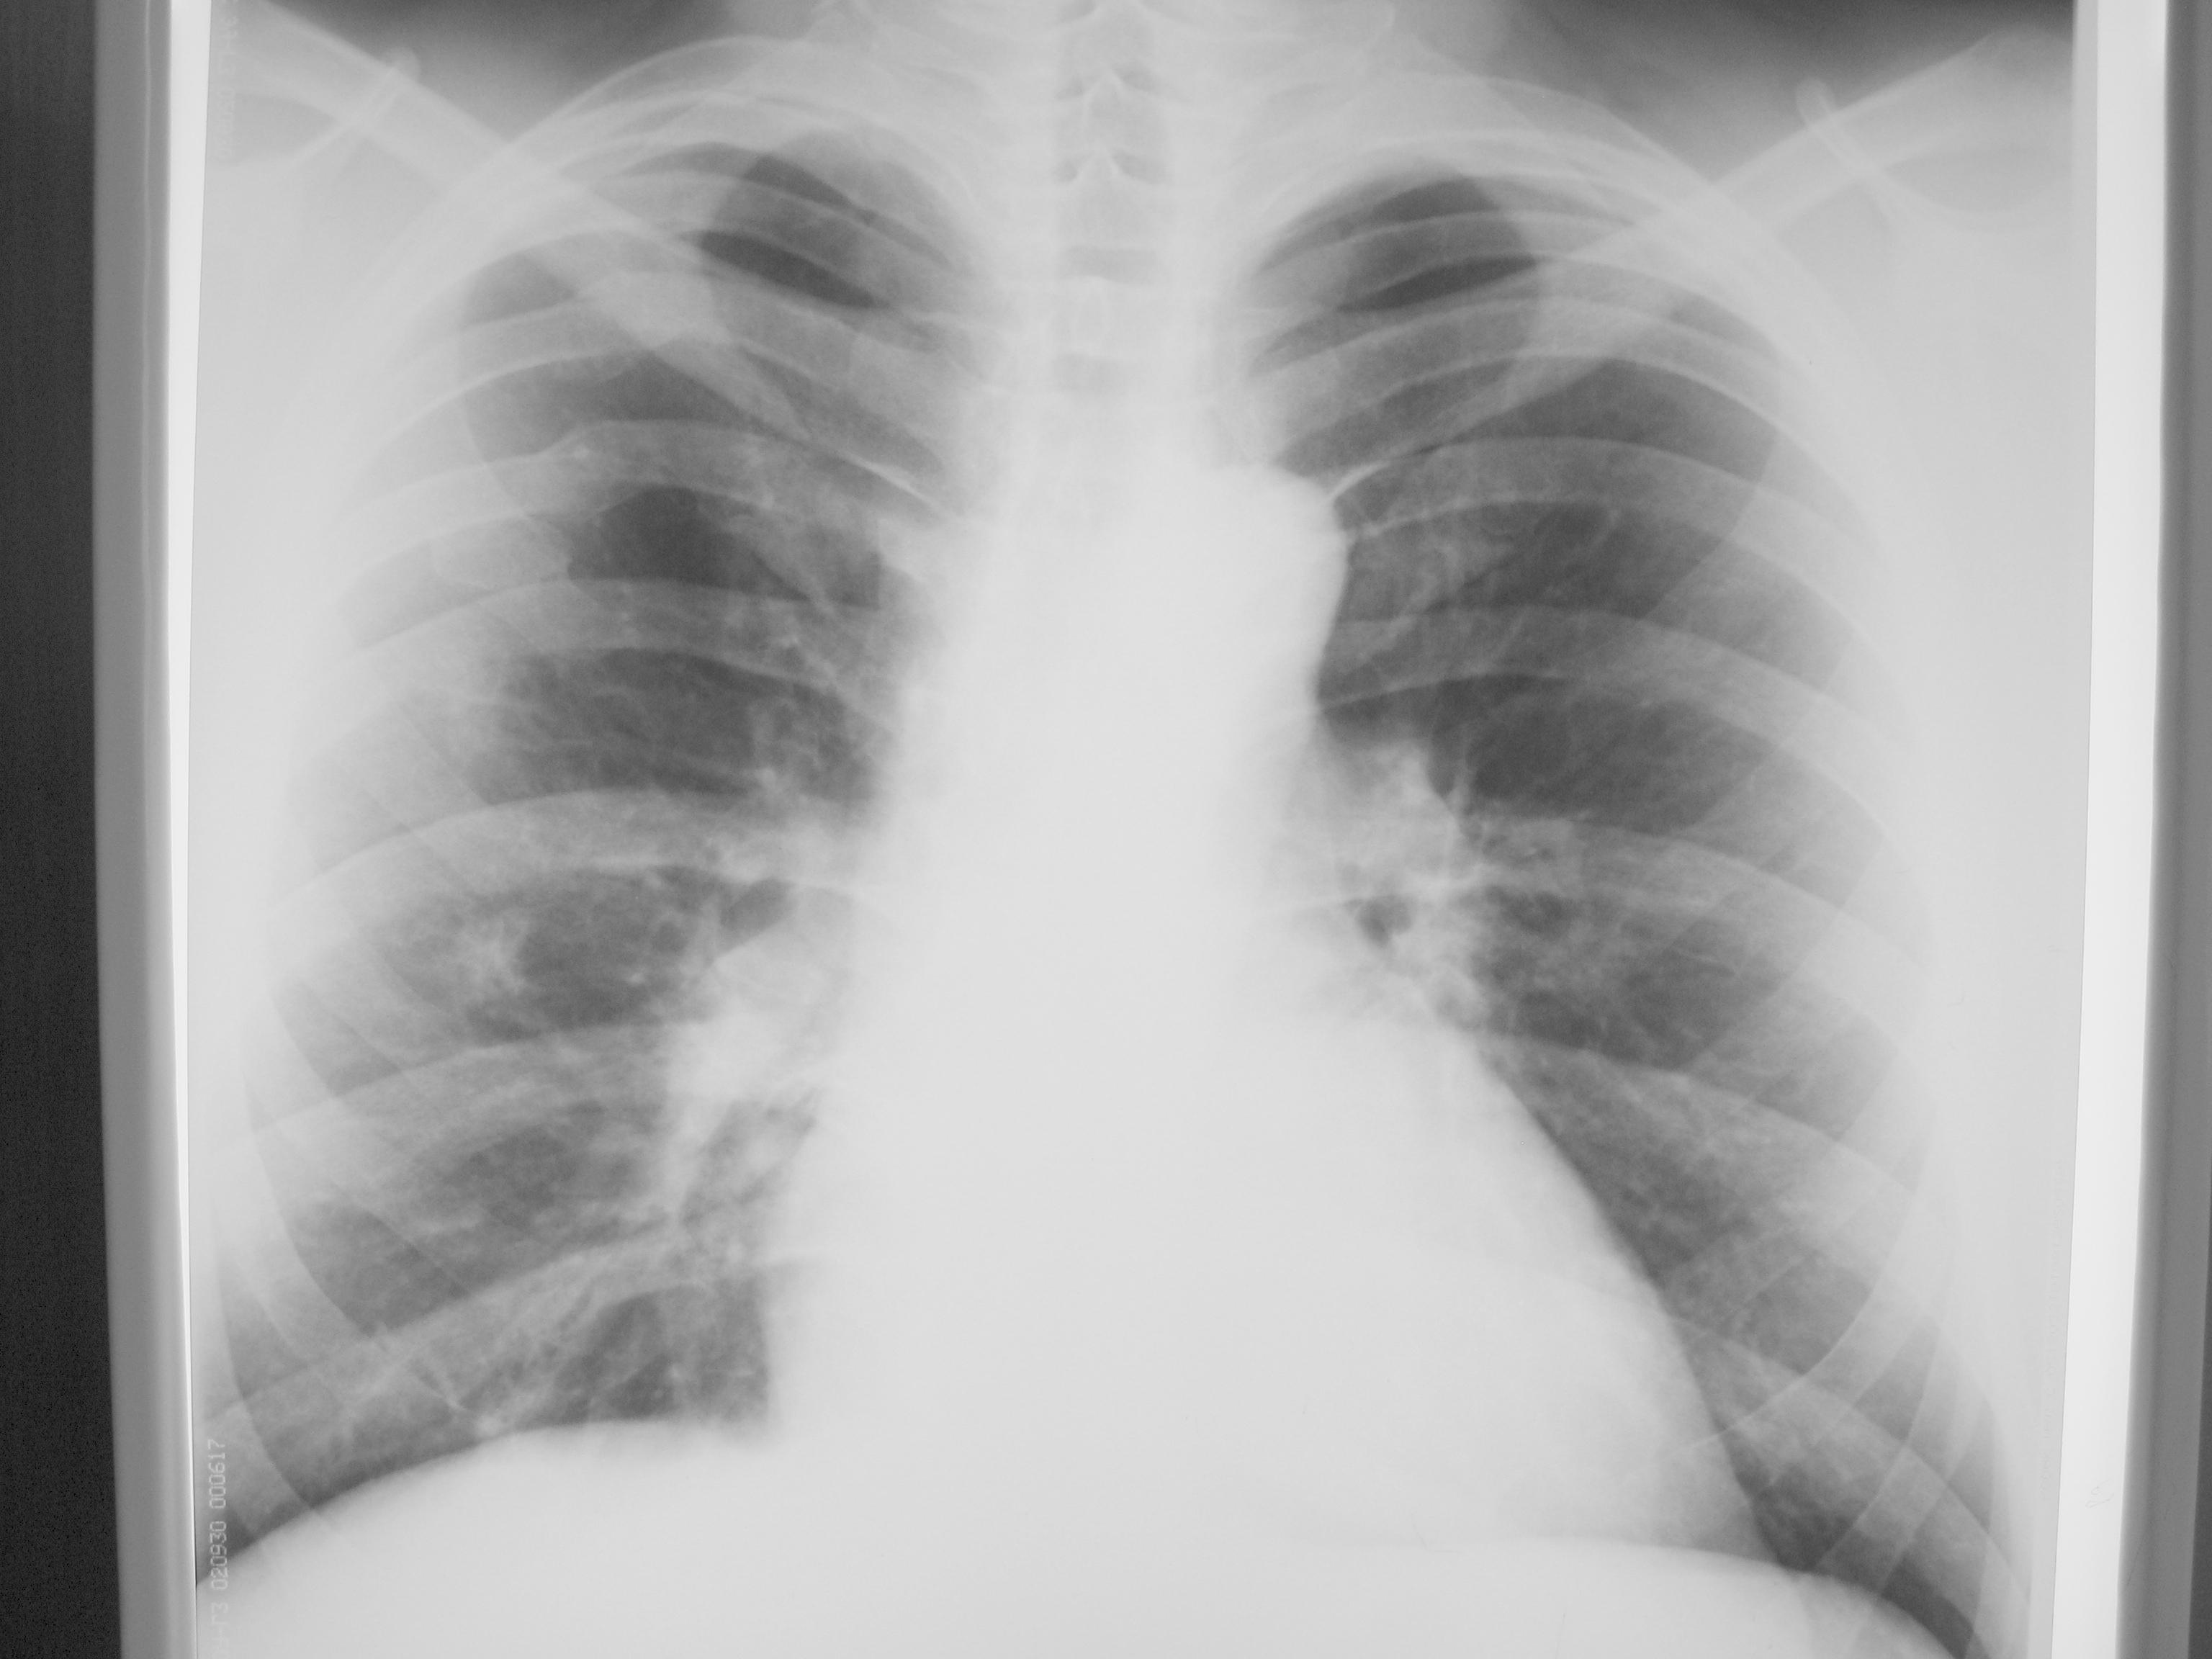

Пациент 1978 г.р, профосмотр, жалоб нет, тяжелой сопутствующей патологии нет, благополучный. Пневмониями со слов не болел, внешне пышущий здоровьем.

ФЛГ от февраля 2011

Тени - ретикулонодулярные? Верхняя в S3, нижняя - непонятно. Тени обусловлены воспалением интрерстициальной ткани, или последствием воспаления в виде фиброза? Может ли это быть инфильтративным туберкулезом?

А четверг что, день патологии легких ?) Прямо как на подбор ) Похоже инфильтраты, по-моему, в С 3, правда четко не вижу; возможно ТВС. Для уточнения сделала бы томографию. Откуда у "благополучного" пациента множественные переломы ребер ? Хотя в жизни всякое бывает.

Для начала, конечно, можно и пневмонию полечить.Но тени не красивые.О периферическом раке думается.

Больше склоняюсь к tbc

Так и 2012г. была тень слева. В сегментах 3 и 8 затемнения неправильной формы, с неровными нечеткими контурами есть. Определиться с этиологией проблемно из-за нехарактерности расположения. Методически, ИМХО пишем: "пневмония в ... + контроль после лечения". Потом остальное будем.

Есть фокусы, мутные вовлечённые корни... А быть может, ещё есть мелкие очаги.

Дифф. диагноз между tbs и раком (или mts). Напишите, чем дело кончится.

склоняюсь к онкологии, больше за мтс, но может быть и первичная нео легкого с мтс. КТ, консультация онколога, обследование по органам и системам. ТБ мало вероятен, почти не вероятен

согласна с данным мнением, правый корень не реагирует, при твс должен, и локализация - S8, S3 без старого твс архива редко при твс, конечно, могу ошибаться, как все, но склоняюсь к мнению периферического с-ч правого легкого с внутриорганным мтс.